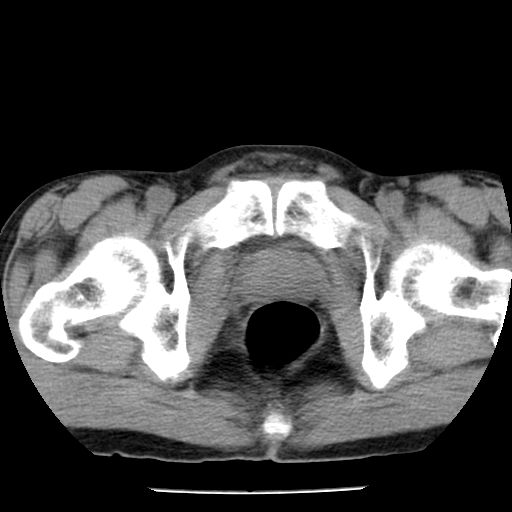

男,59岁,“结核性胸膜炎”30余年,胸部经常疼痛,多次x检查提示“肺部”炎症。腹部疼痛5日,b超提示:“肝内短管结石,余显示不清,建议进一步检查。”

胸部腹部都是结核(双肺。纵隔淋巴结,肝脏,脾脏,肠系膜)

两肺结核并右侧胸腔积液;脾脏、腹腔及腹膜后淋巴结结核[陈旧性];肝内胆管结石。直肠息肉?